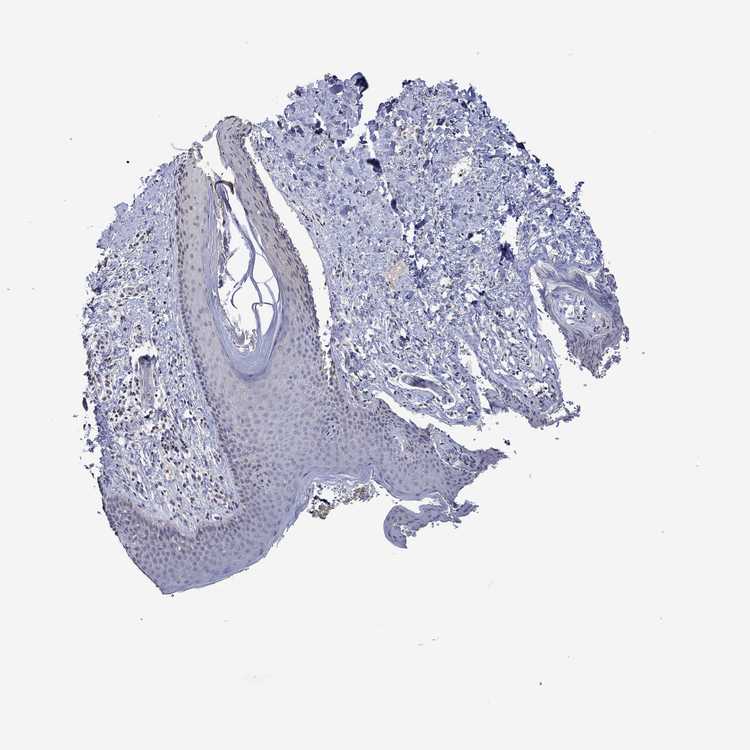

SKIN 1 - Antibody stainingi

Antibody staining in the annotated cell types in the current human tissue is reported as not detected, low, medium, or high, based on conventional immunohistochemistry profiling in selected tissues. This score is based on the combination of the staining intensity and fraction of stained cells.

Each image is clickable and will lead to virtual microscopy that enables deeper exploration of all samples and also displays staining intensity scores, fraction scores and subcellular localization as well as patient and tissue information for each sample.

Antibody HPA043337Antibody HPA048310Antibody HPA069148

Langerhans LowLowNot detected

Fibroblasts LowNot detectedNot detected

Keratinocytes LowLowNot detected

Melanocytes LowLowNot detected

SKIN 2 - Antibody stainingi

Epidermal cells MediumNot detectedNot detected